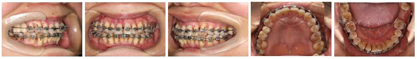

经过矫正前的牙周系统治疗以及22个月的矫正加稳定并联合矫治期间定期的牙周维护治疗,矫治结束后患者上下牙列牙齿排列整齐,建立了正常的覆牙合覆盖,维持了双侧磨牙、尖牙咬合关系,未有咬合干扰点,达到稳定的咬合关系。同时,牙周袋并未加深,11瘘管愈合(图2),全口牙龈颜色正常,牙周组织无活动性炎症出现,另外,患者口内治疗前多颗松动的牙齿,其松动度也有明显的改善,例如治疗前11、22松动Ⅲ°,23松动Ⅱ°,12、36~41松动Ⅰ°。治疗后11、22松动Ⅰ°,其余牙齿稳定无松动现象。X线表现(图9)治疗后牙槽骨吸收停止且23~26近远中,36远中以及27近中等部位均有少量牙槽骨再生,骨白线连续性亦有增加,下前牙区牙槽骨高度有少量增加。关节矢状面、冠状面保持稳定,FloridaProbe牙周检查最终探诊深度普遍降至1~3 mm。X线头影测量前后对比以及重叠图可见上前牙内收较明显,下切牙压低有效,侧貌突度明显改善(图10,图11,图12,图13,图14)。